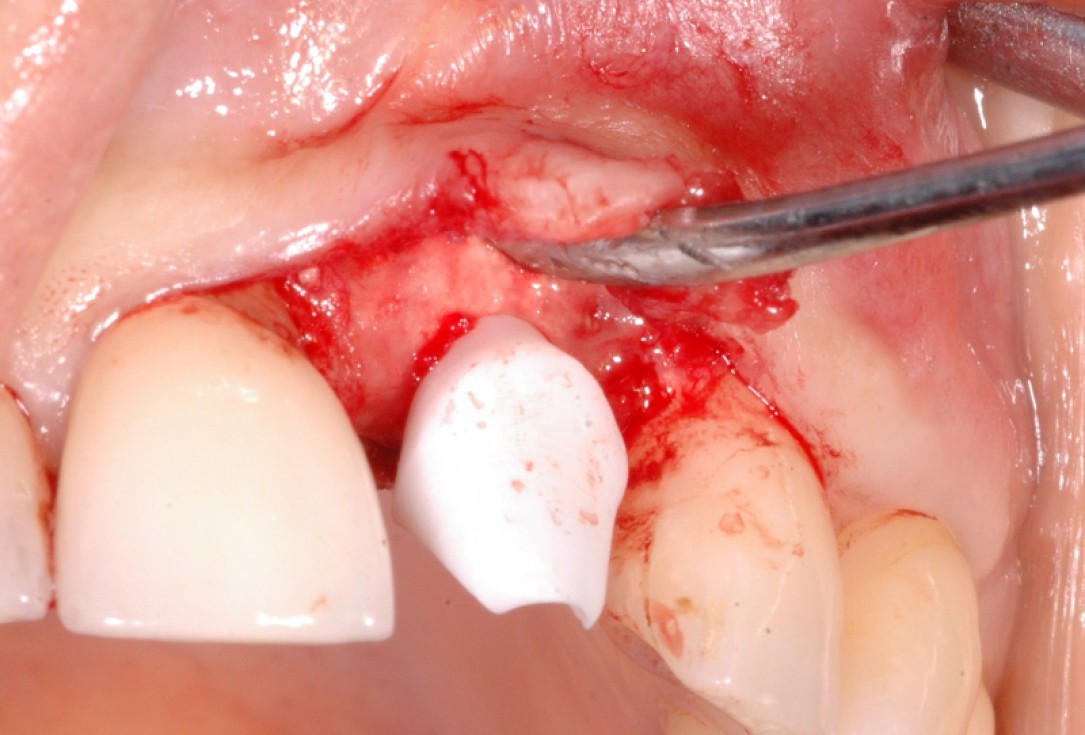

13/18 - Further soft tissue augmentation with mucoderm®GBR together with soft tissue augmentation with mucoderm® and maxresorb® - Dr. S. Scherg

14/18 - Wound closure and mounting of provisional prosthesisGBR together with soft tissue augmentation with mucoderm® and maxresorb® - Dr. S. Scherg